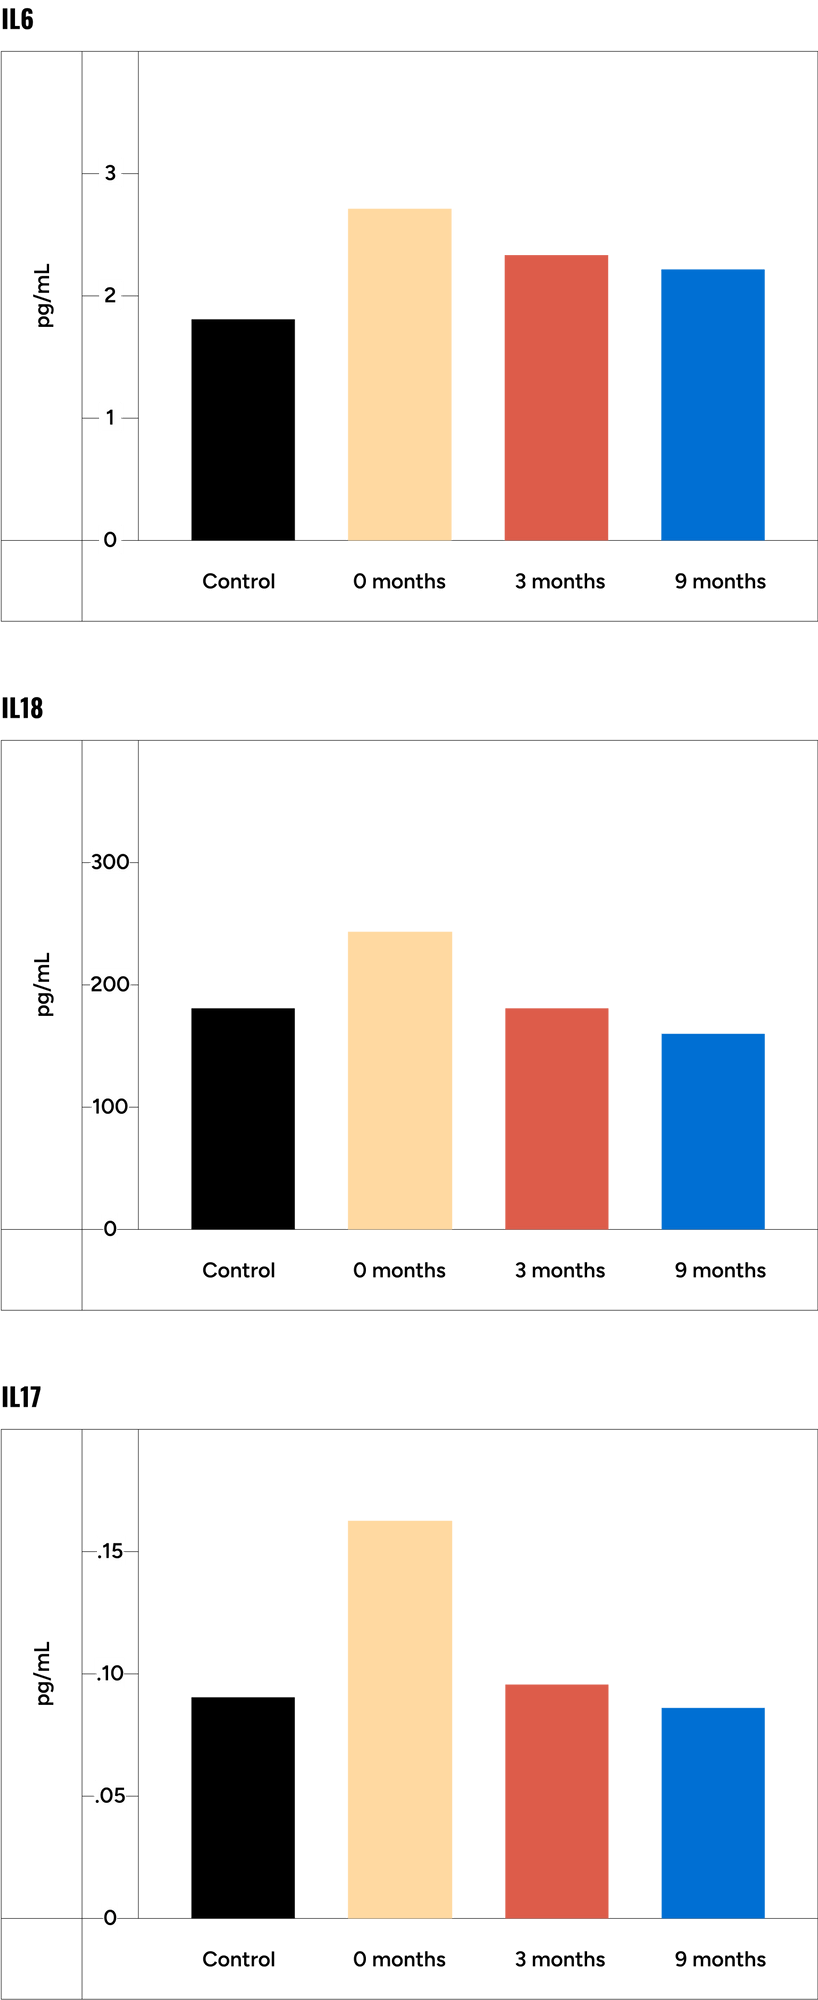

Chronic conditions accumulate as we age, and PDE5 inhibition has been proven to slow or halt this regression in health, lowering the risk of cardiovascular disease and Alzheimer’s Disease. This study shows that tadalafil increases cognition through its anti-inflammatory effects, while this animal study revealed tadalafil’s ability to cross the blood–brain barrier helped to reverse cognitive dysfunction. Tadalafil is also found to be more beneficial than other PDE5 inhibitors for memory impairment, including Viagra, because of its longer half-life and proven safety, representing “a promising approach for the chronic treatment of cognitive disorders.”

Tadalafil Reduced Proinflammatory Interleukins Associated with Cognitive Decline

Fig.3 - Urios A, Ordono F, Garcia-Garcia R, et al. Tadalafil treatment improves inflammation, cognitive function, and mismatch negativity of patients with low urinary tract symptoms and erectile dysfunction. Sci Rep. 2019;9(1):17119.